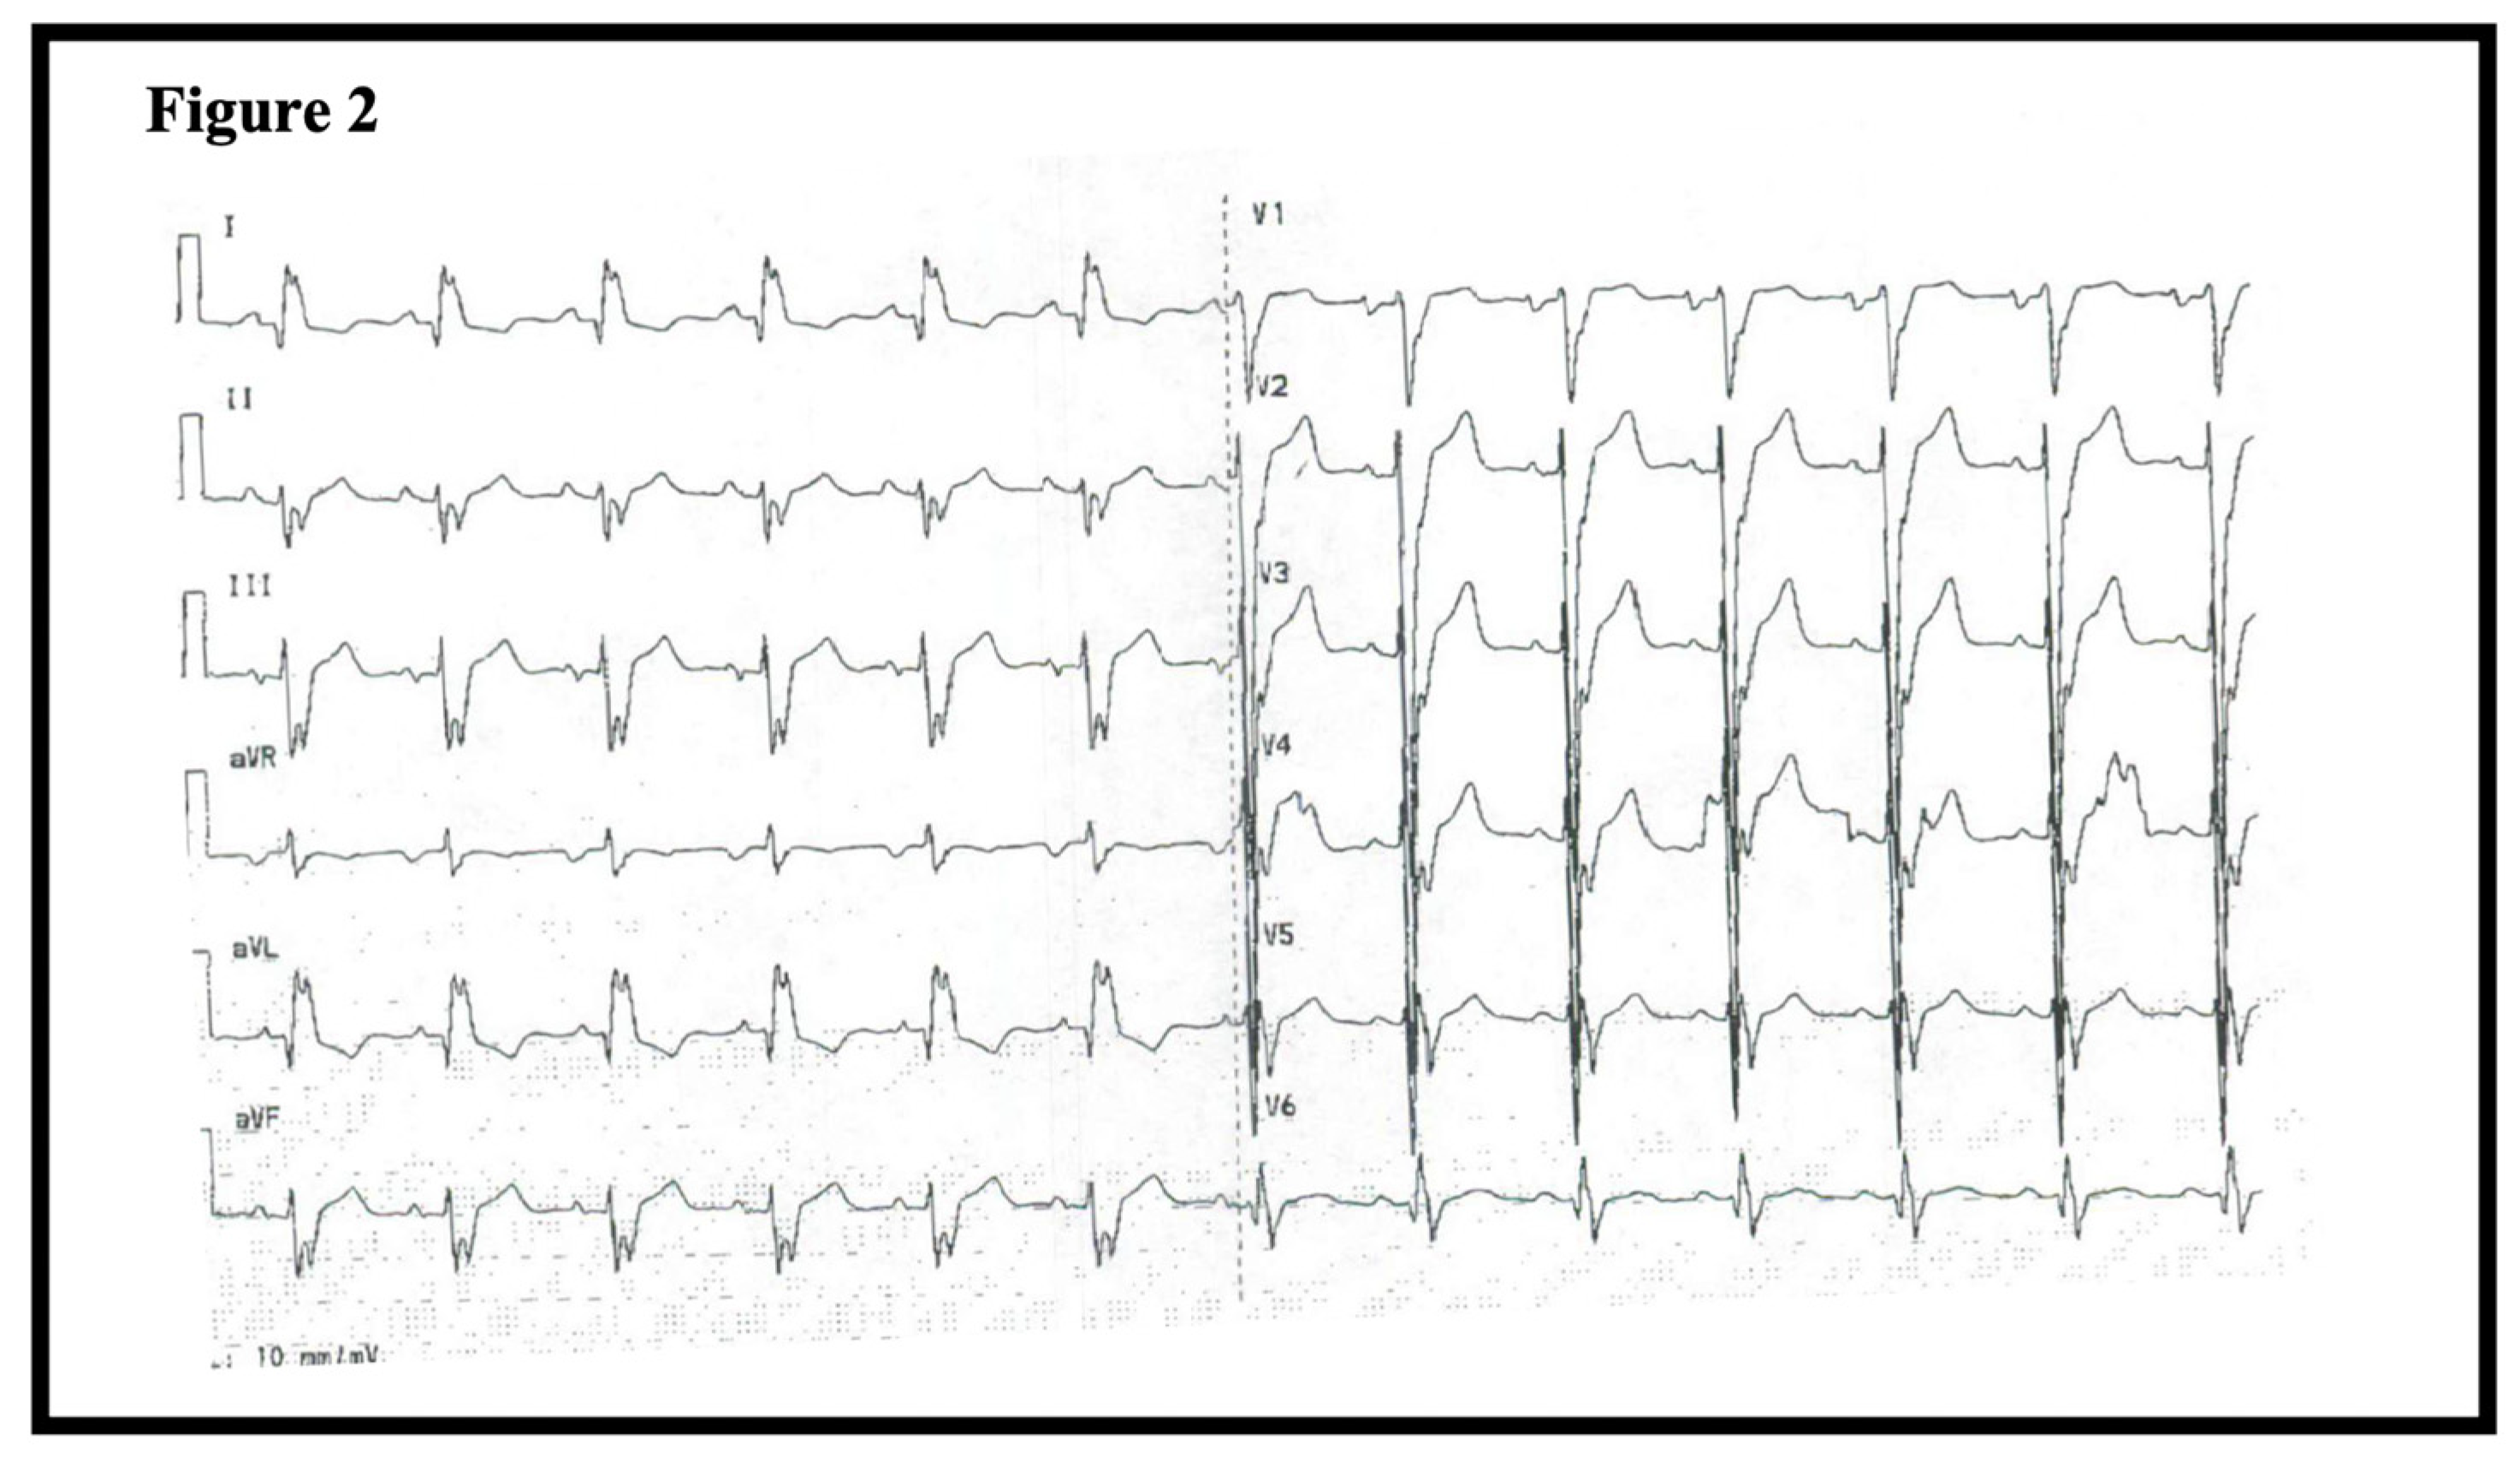

At the time of admission in 2011, the patient was hemodynamically stable (blood pressure 116/69, heart rate 100) and presented with a fever leading to initiation of antibiotic treatment due to suspicion of pneumonia. Routine blood testing including cardiac troponins, hematological, and kidney biomarkers were unremarkable. However, an ECG showed intraventricular conduction defect with a QRS-duration of 150 ms (Figure 2). A chest radiograph revealed cardiomegaly (Figure 3A). Subsequently, an echocardiography demonstrated severe left ventricular (LV) dilation with an end-diastolic diameter of 82 mm (indexed 41 mm/m2) and a LV ejection fraction (EF) of 10% (Figure 3B). These findings led to the initiation of anti-congestive medical treatment and later implantation of a cardiac resynchronization therapy-defibrillator. Further diagnostic work-up included genetic screening, right heart catheterization, and coronary angiography. The right heart catheterization showed a reduced cardiac index (1.8 L/min/m²) and elevated cardiac chamber filling pressures (right atrial pressure of 12 mmHg, mean pulmonary artery pressure of 47 mmHg, and wedge pressure of 31 mmHg). The coronary angiogram was normal, and the myocardial biopsy showed histologic features consistent with dilated cardiomyopathy with severely hypertrophic cardiomyocytes (Figure 4A–C).

Figure 2.

ECG of patient 1 at admission time showing an intraventricular conduction defect.